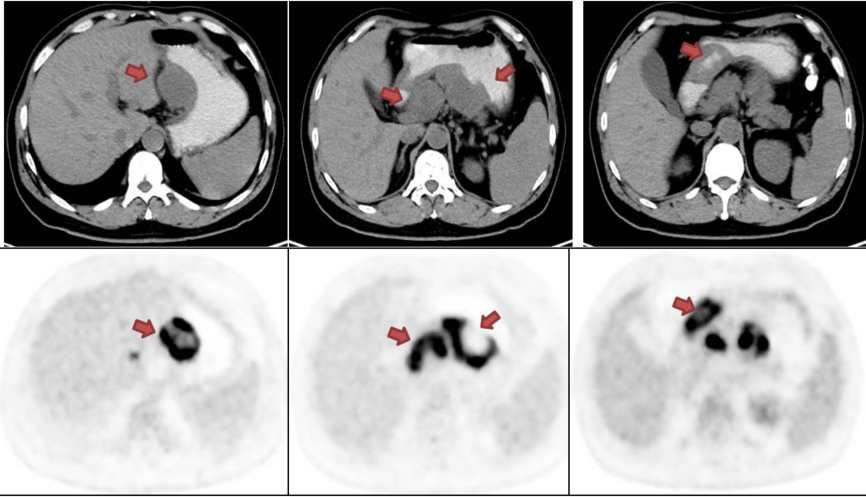

完成3周期新辅助治疗后(2023年12月),复查影像学评估,临床分期降至ycT1-3N0M0。

930.8.png

图2 完成3周期新辅助治疗后疗效评估